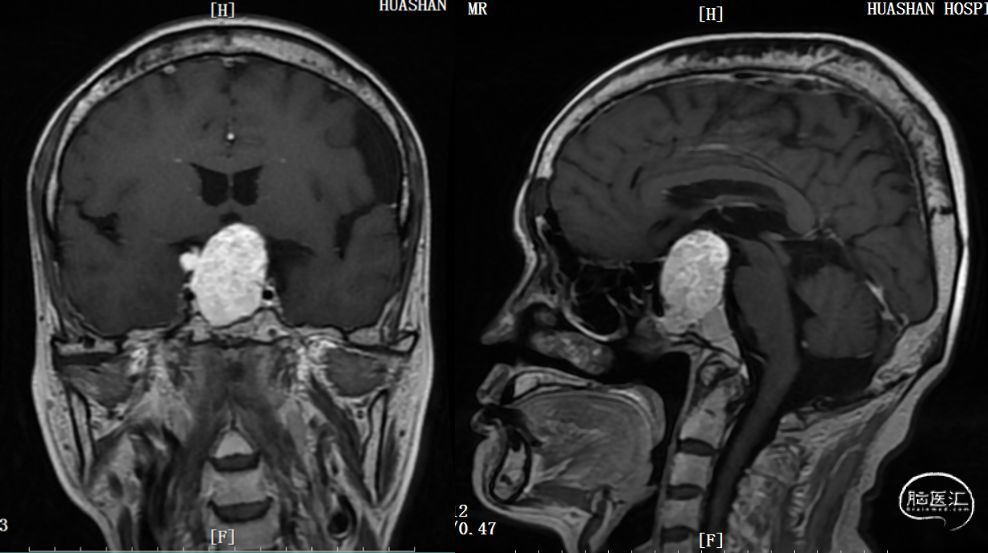

患者老王今年50岁,来自河南。2013年起老王出现消瘦,并有心慌、怕热、手抖,然而这没有引起他的重视。随着症状加重,三年之后。老王在当地医院查出有心房颤动,是一种心律失常,可是治疗后心脏不适没有明显改善。直到2019年5月,老王不幸遇到车祸,到医院做头颅CT和磁共振,居然发现有个巨大的垂体瘤,并且是一种罕见的分泌促甲状腺激素的腺瘤,正是因为这个肿瘤导致老王出现了心脏疾病。由于垂体促甲状腺激素腺瘤在临床上极少见,常引起误诊、漏诊,延误了治疗时机。

老王随后慕名求诊于华山医院神经外科王镛斐教授。考虑到患者病情较重、病程漫长,需进行充分的术前评估与准备,王教授立即联系了华山金垂体融合病房的内分泌科,内分泌科通过功能性垂体瘤诊疗绿色通道迅速安排患者入院评估。老王于2019年6月收入内分泌科,经一系列详细检查,明确是垂体促甲状腺激素腺瘤。由于肿瘤巨大,已明显压迫视神经,导致视力下降和视野缺损,应尽快接受手术治疗。内分泌科张朝云教授与王镛斐教授进行了第一次病例讨论,考虑到患者甲亢没有得到控制,甲状腺激素水平很高,此时手术风险大,很容易导致甲状腺危象的发生,而甲状腺危象的死亡率高达20%以上。内外科讨论后决定了治疗方案:先由内分泌科尽快控制甲亢,然后予以手术切除肿瘤。